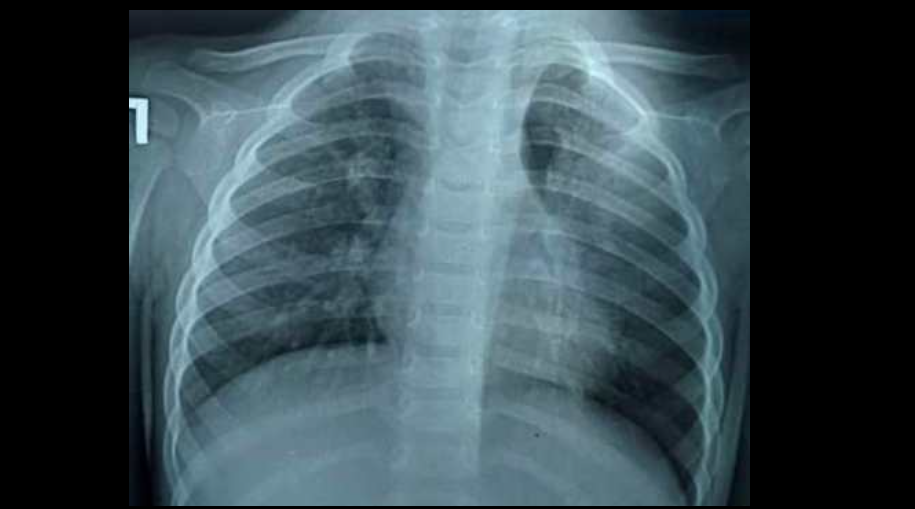

Бишкекте 1 жаш 10 айлык баланын өпкөсүнөн жүгөрүнүн даны табылганын балдар хирургу Калыбек Мыкиев социалдык тармактагы баракчасында билдирди.

"Ата-энелердин эсине! Өзгөчө кичине балдары барларга! 3 айдан бери ар кайсы жакта дарыланышкан, көп антибиотик алышкан, акырында бүгүн 14-июлда бронхоскопия жасап сол бронхтон жүгөрү алып чыктык. Толтура ириң кан. Дагы жасалышы мүмкүн. Дагы 3-4 ай жүргөндө сол өпкө жарабай калмак. Балдарга көз салгыла, ата-энелер",— деп жазды ал.